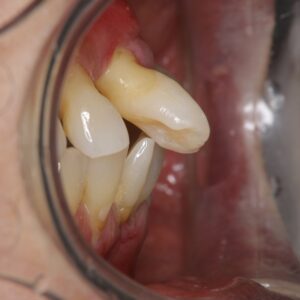

治療前 下顎両側大臼歯欠損は放置され、上下顎前歯は前方に傾斜・突出した状態であり、上顎の右側中切歯は動揺が著明で、全顎的に歯肉の発赤・腫脹がありました。

1. 初診相談

デンタルレントゲン写真と歯周組織検査の結果から、重度の歯周炎に罹患しており(広汎型 重度慢性歯周炎 ステージⅣグレードC)していました。口腔清掃不良による歯周炎の進行と、下顎両側大臼歯の欠損放置に伴って前歯部に噛み合わせの力が強くかかり(二次性の咬合性外傷)、歯槽骨吸収が進行するとともに上下顎ともに歯の病的な位置異常が生じたと考えます.主訴である上顎右側中切歯は、抜歯が適当と考えました。